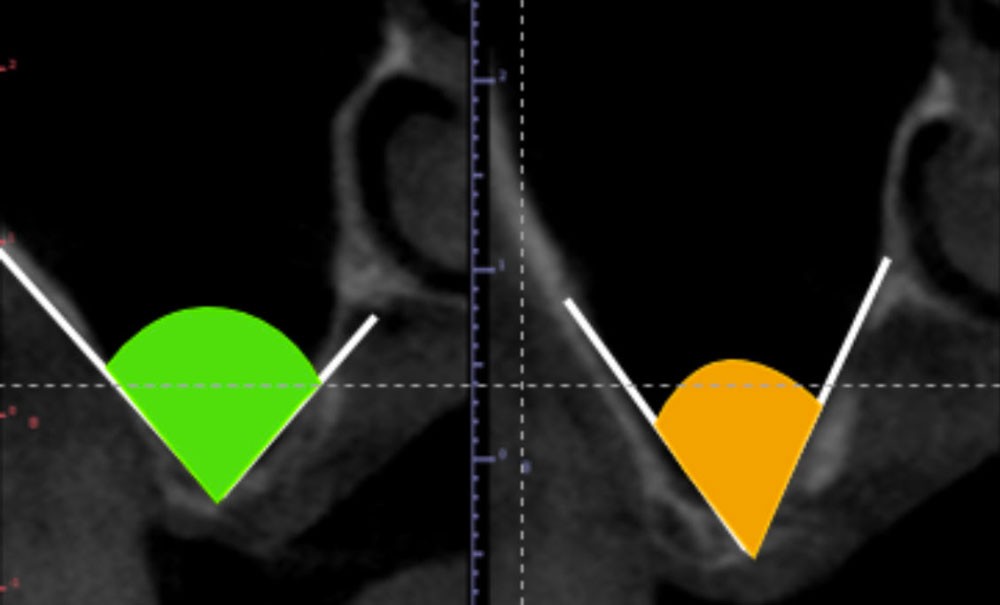

L’implantologie en région molaire maxillaire reste un défi pour beaucoup de chirurgiens-dentistes. En effet, la proximité avec la cavité sinusienne peut compliquer l’intervention et freiner certains praticiens. L’une des options thérapeutiques pour la pose d’implant sous-sinusien est la réalisation d’un soulevé sinusien appelé aussi sinus lift. L’objectif de cette conférence était l’illustrer, à travers une chirurgie en direct sur le site du Palais des Congrès, les étapes clefs de cette intervention.

• le troisième point traite des facteurs de succès chirurgicaux généraux : indication de la pose d’implants avec le respect du projet prothétique, environnement parodontal favorable, respect des procédures chirurgicales (flap design préalable, définition de la position de la fenêtre d’accès, élévation de la muqueuse avec une séquence d’instruments spécifiques, l’objectivation d’absence…